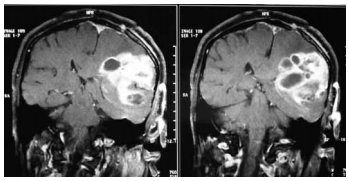

Uma mulher com cinquenta e três anos de idade foi admitida em um hospital apresentando, havia dois meses, quadro de cefaleia, hemiparesia à direita, náuseas e dificuldade na fala — todos de caráter progressivo. A paciente negou febre e não houve crise convulsiva nem alterações comportamentais. Os resultados do exame de ressonância magnética contrastada do crânio são mostrados na figura precedente. Com relação a esse caso clínico, julgue o item seguinte considerando o resultado das imagens. No caso em questão, caso ocorram síncopes causadas por tosse, espirros ou por vômitos, elas refletirão reduções temporárias da pressão de perfusão cerebral, associadas a ondas platô — tipo A de Lundberg — na pressão intracraniana.